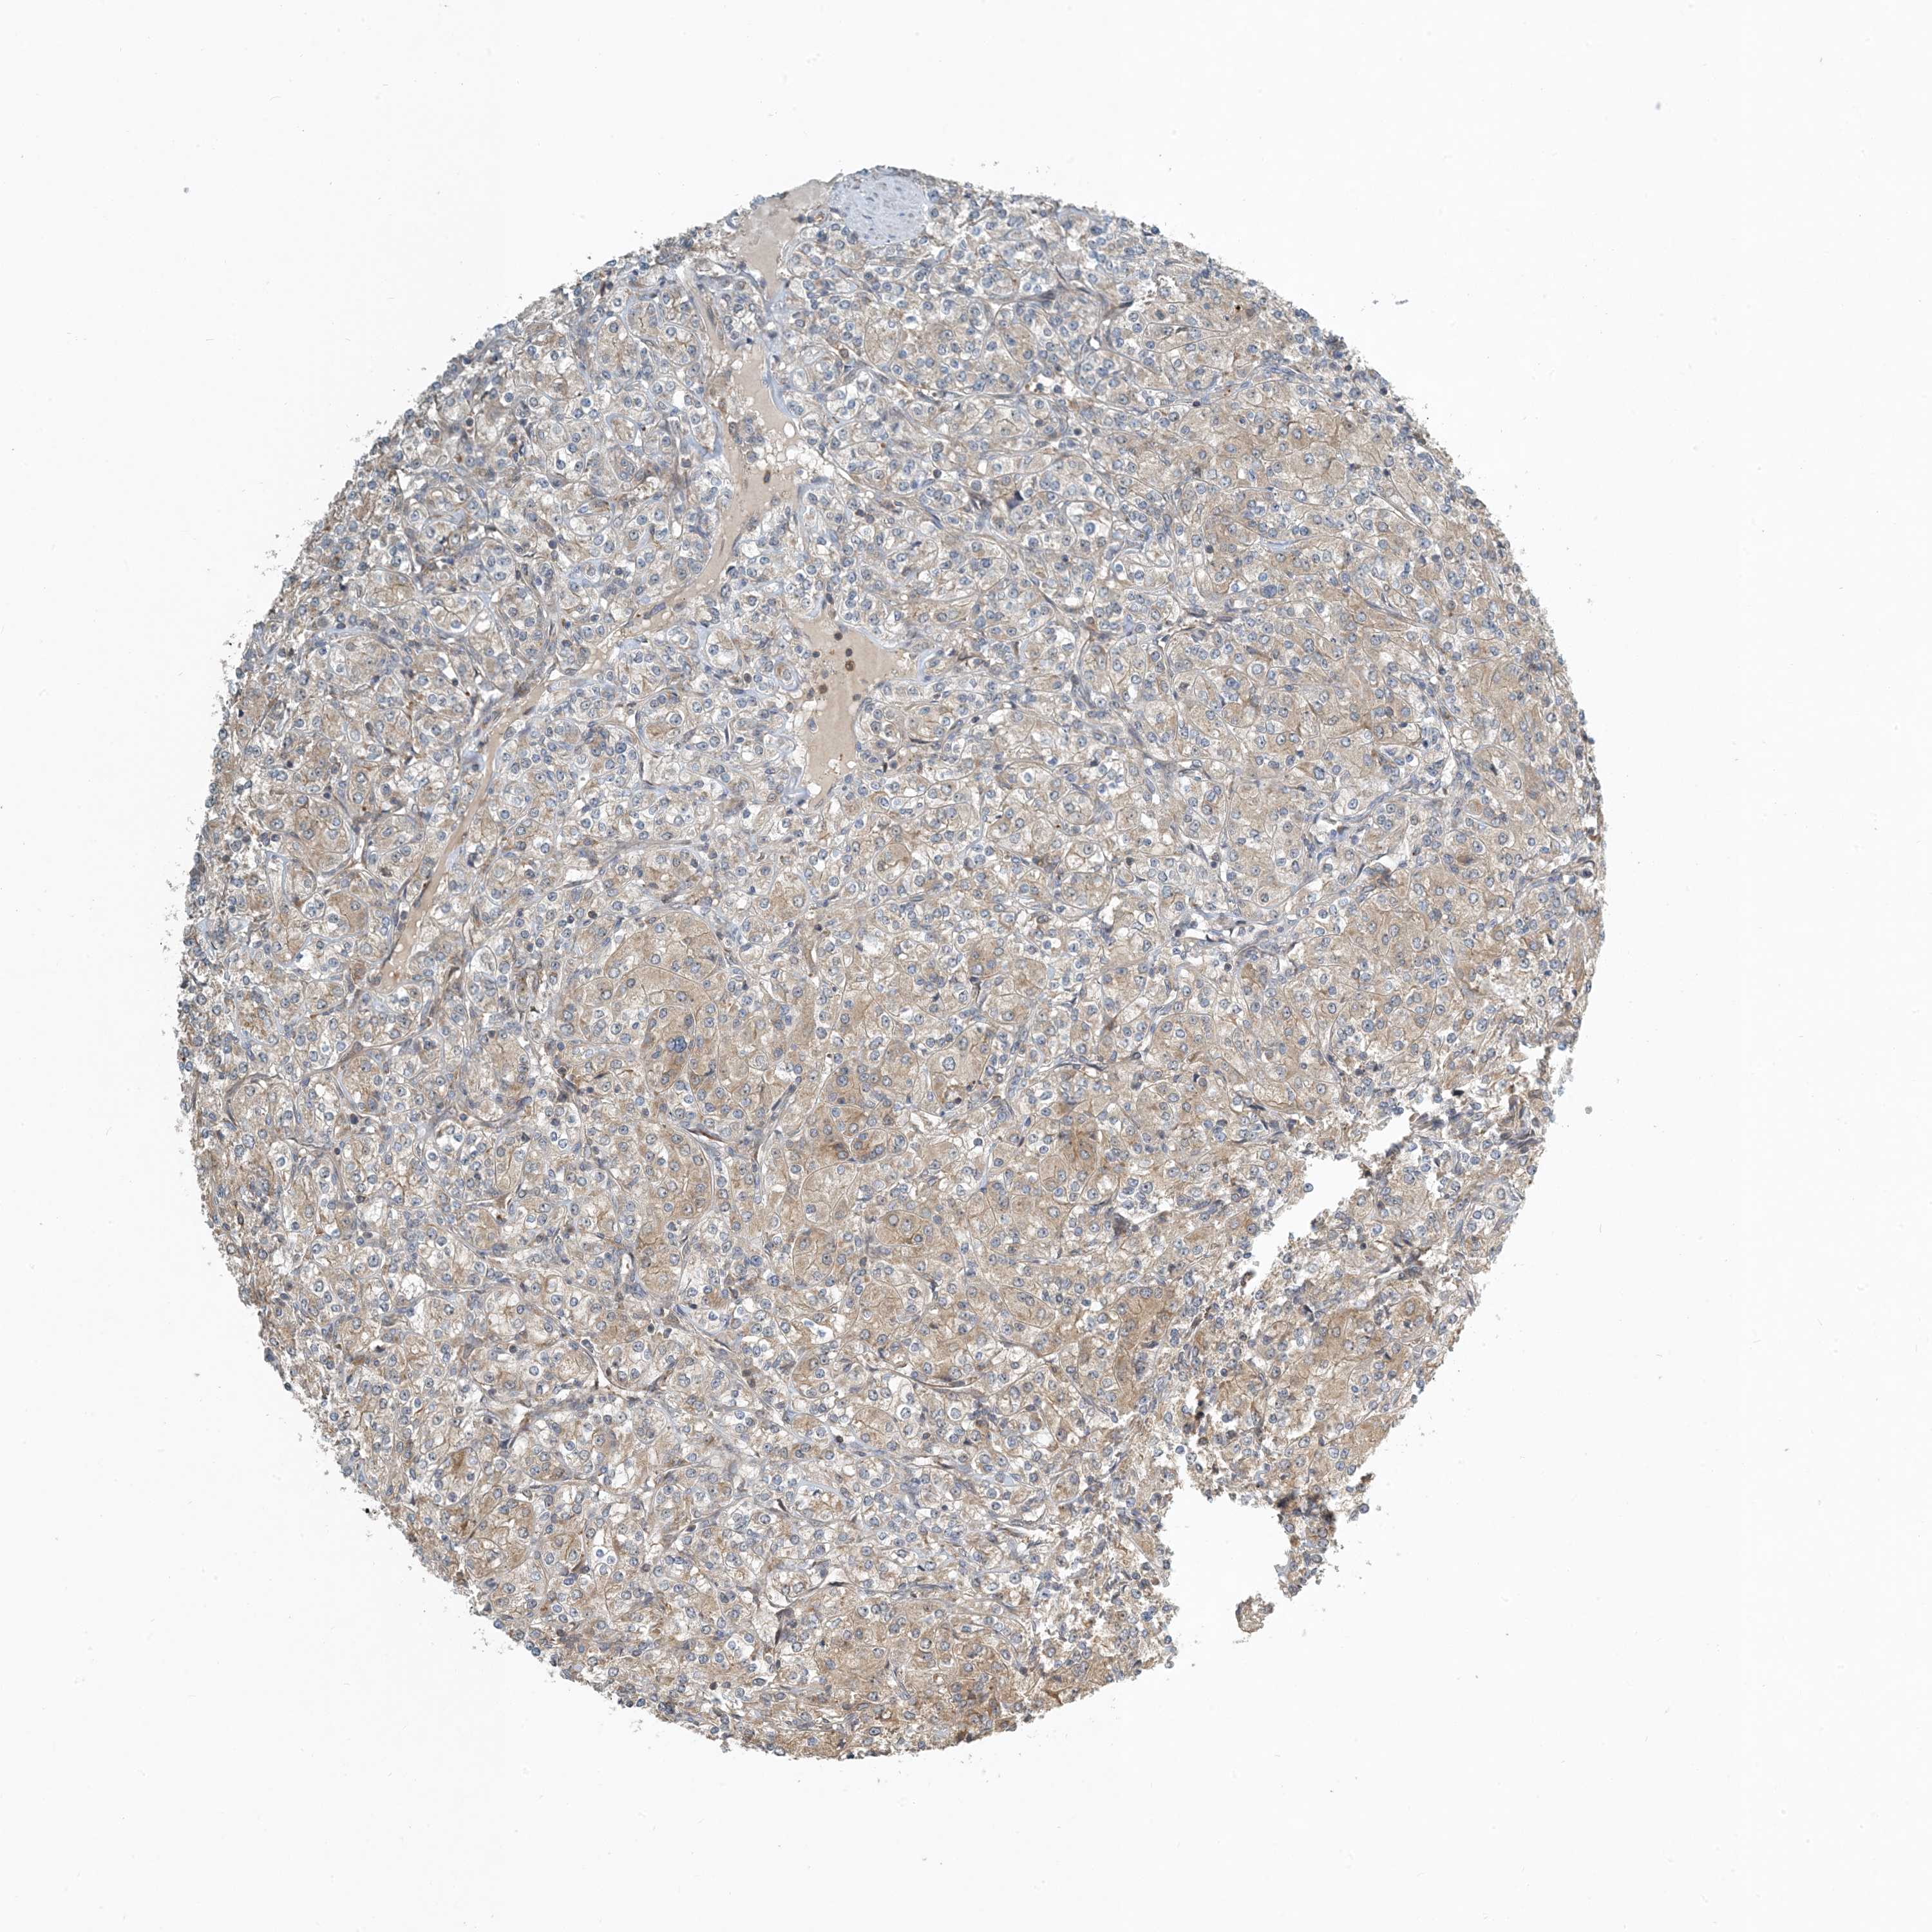

CANCER RENAL CANCER Show tissue menu